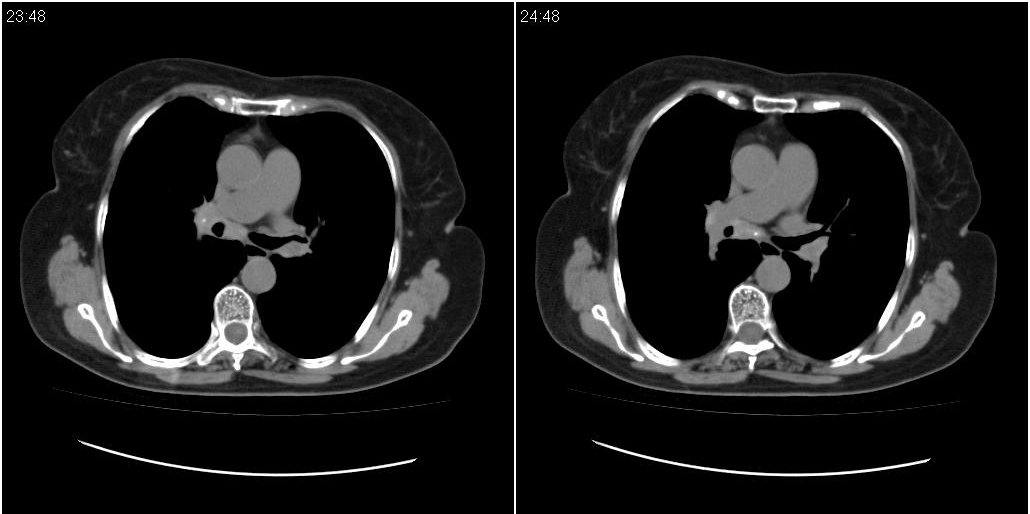

女性,72岁。去年9月份发现肺部病变,诊为肺结核并进行正规治疗至今,但复查后发现ct表现几乎没有变化。

右中间段支气管局限性狭窄,右中叶支气管亦稍显狭窄,但并未见明显占位表现,半年多了,无变化也许是好事,可能为炎性狭窄,建议继续随访。

双肺继发型tb并右中叶内膜tb,轻度支扩,左下胸膜肥厚粘连。

右中叶炎性改变,支气管狭窄但较光滑,占位可能性不大。

双肺继发性肺结核并右肺中叶节段性肺不张,左下胸膜肥厚粘连。

右肺中叶节段性肺不张,考虑结核或慢性炎症,建议做纤支镜检查。

双肺继发性肺结核并右肺中叶节段性肺不张